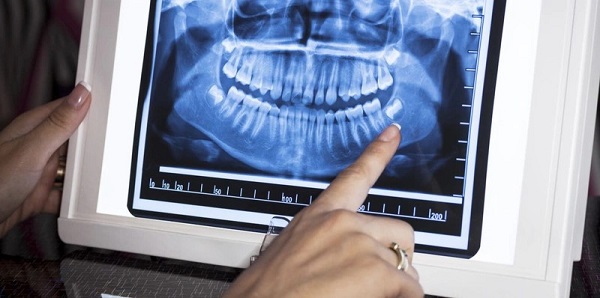

Quy trình thực hiện chụp X quang răng

Hướng dẫn đọc kết quả chụp X quang

Sau khi chụp X quang, bác sĩ sẽ xem và đọc kết quả. Họ sẽ giải thích cho bạn về các vấn đề được phát hiện và trả lời những câu hỏi liên quan đến sức khỏe răng miệng. Nếu bạn có bất kỳ câu hỏi nào về kết quả chụp X quang, đừng ngần ngại yêu cầu giải thích chi tiết hơn về tình trạng của răng miệng và các lựa chọn điều trị.